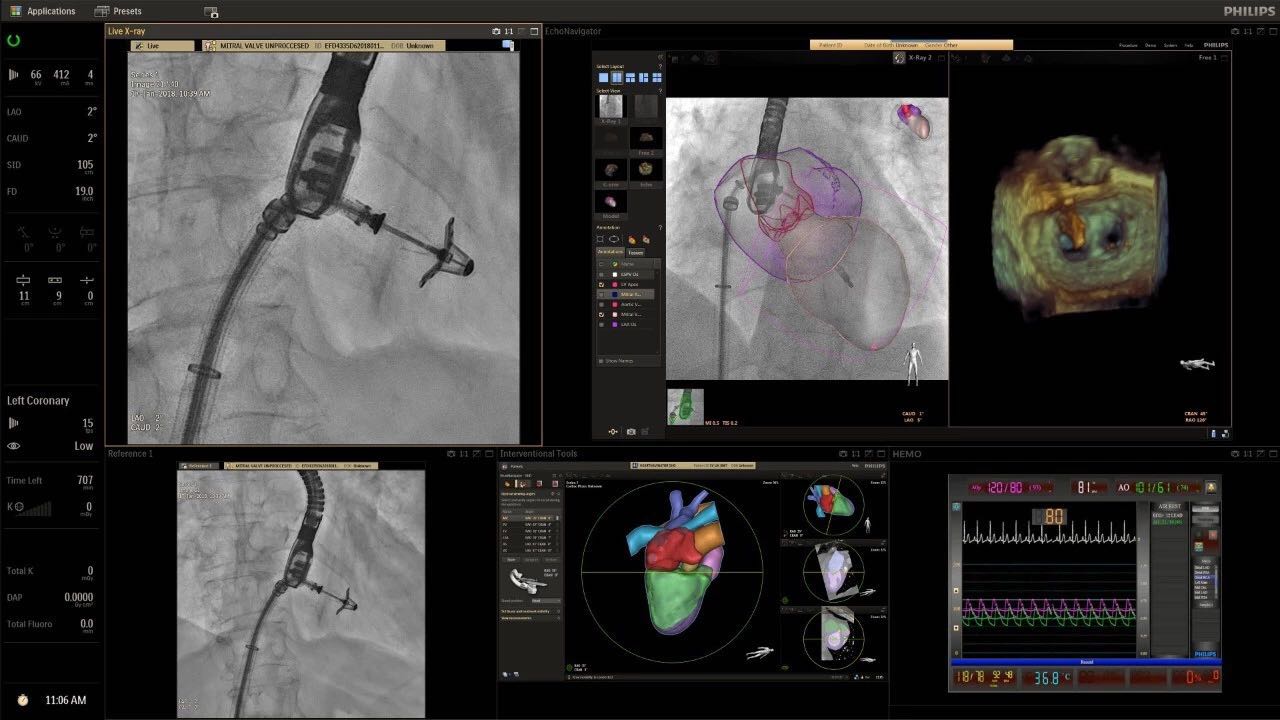

在日益復(fù)雜的干預(yù)期間,臨床醫(yī)生需要快速、輕松地可視化關(guān)鍵解剖結(jié)構(gòu)并確定手術(shù)過(guò)程中患者的變化。2019年1月17日,飛利浦宣布推出采用FlexArm的Azurion 7 C20,旨在提高圖像引導(dǎo)程序的定位靈活性。

帶有FlexArm的Azurion 7 C20 包含一系列創(chuàng)新技術(shù),使臨床醫(yī)生可以更輕松地在整個(gè)患者身上進(jìn)行二維和三維成像。當(dāng)臨床醫(yī)生移動(dòng)系統(tǒng)時(shí),圖像光束自動(dòng)保持與患者的對(duì)準(zhǔn),允許更一致的可視化并使他們能夠?qū)⒆⒁饬性谥委熒稀?/span>

可通過(guò)微創(chuàng)手術(shù)治療的疾病的范圍和復(fù)雜性繼續(xù)擴(kuò)大。相應(yīng)地,程序本身也變得更加復(fù)雜,需要來(lái)自不同學(xué)科的更多醫(yī)生在患者的桌邊,以高度協(xié)調(diào)的方式一起工作。因此,臨床團(tuán)隊(duì)需要在高度受限的環(huán)境中執(zhí)行越來(lái)越具有挑戰(zhàn)性的程序。

飛利浦表示,采用FlexArm設(shè)計(jì)的Azurion 7 C20可提供卓越的靈活性和直觀的控制。該系統(tǒng)由智能運(yùn)動(dòng)引擎驅(qū)動(dòng),可在八個(gè)不同的軸上移動(dòng),所有這些軸均由其單個(gè)“Axsys”控制器控制。臨床醫(yī)生的模擬測(cè)試表明,該系統(tǒng)有可能顯著減少患者,工作人員和設(shè)備的重新定位,從而改善微創(chuàng)手術(shù)的可及性,包括通過(guò)患者手腕進(jìn)入身體的手術(shù)(橈動(dòng)脈入路),并降低患者的風(fēng)險(xiǎn)。無(wú)意中拔出電線和管子,以及節(jié)省大量時(shí)間。該系統(tǒng)非常適合混合手術(shù)室(OR),可滿足一個(gè)房間內(nèi)的多種專業(yè)需求,例如手術(shù)和血管內(nèi)手術(shù)的組合。

FlexArm在不少于8軸的情況下旋轉(zhuǎn),從而創(chuàng)建幾乎無(wú)限的靈活性來(lái)執(zhí)行成像,從頭部到腳部在左側(cè)和右側(cè)進(jìn)行2D和3D可視化。圖像光束保持與患者對(duì)齊,允許在旋轉(zhuǎn)或角度期間更好地可視化解剖結(jié)構(gòu)。使用Axsys運(yùn)動(dòng)控制系統(tǒng)輕松操作支架。